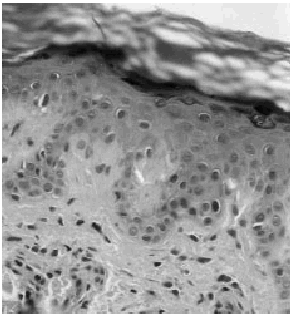

Mujer de 52 años, con antecedentes de accidente cerebrovascular sufrido hacía 10 años, que consultó por presentar desde hacía más de 2 años áreas hiperpigmentadas y pruriginosas en el tercio superior de la espalda. Con la sospecha clínica de amiloidosis maculosa se realizó una biopsia cutánea. En ella se observó una hiperpigmentación de la capa basal y la presencia en las pápilas dérmicas de un material rosado de aspecto cuarteado característico de la amiloidosis maculosa (Fig. 1) junto a cambios focales de hiperqueratosis epidermolítica (Fig. 2). Las tinticiones con Rojo-Congo y citoqueratinas de alto peso molecular fueron negativas.

FIG. 1.--Detalle de los «glóbulos» eosinófilos de amiloide depositados en las papilas dérmicas.